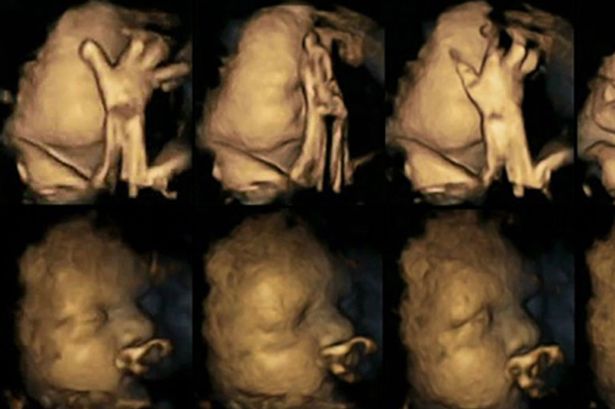

Pas studimit të pamjeve të javës 24, 28, 32 dhe 36, u vu re se fetuset e nënave duhanpirëse lëviznin më shumë pjesën e gojës dhe preknin veten më shumë se fetuset e nënave joduhanpirëse. Këto fetuse gjithashtu mund të shfaqin zhvillim të vonuar në sistemin nervor qëndror.

Fetusi i një nëne duhanpirëse (lart) ; Fetusi i një nëne joduhanpirëse (poshtë)